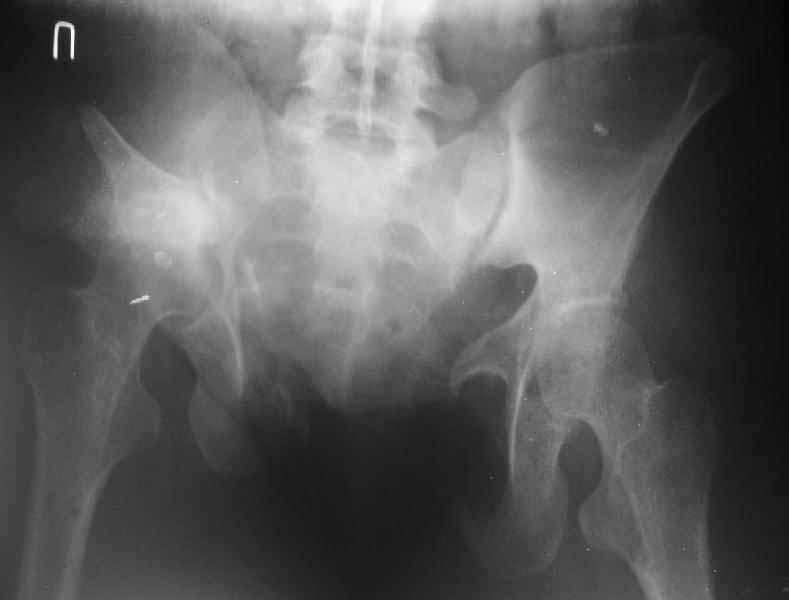

Some additional data. Her main complaints are:

-pain in the left SI joint, the right is painless;

-limb shortening (walks with shoe raise, no walking aid)

-scoliosis and extra-lordosis

-low back pain

-unable to stand more than 20-30 minutes

-unable to sleep without inflatable rubber pad under the sacrum and bolsters under knees.

-unable to sit comfortably

Majeed score is 41.

X-rays and more CT - see attached.